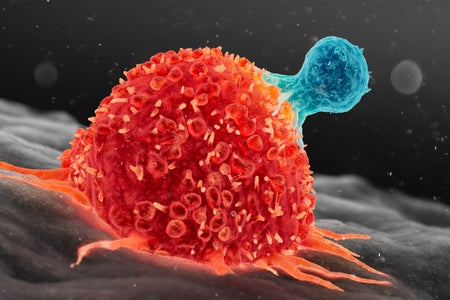

Paxlovid COVID Treatment Most Beneficial for Unvaccinated People with Risk Factors. Others May Not Need It

A recent study suggests that Paxlovid is ineffective at treating symptoms in people with mild illness or those who have been fully vaccinated. It is still a lifesaving medication in vulnerable groups